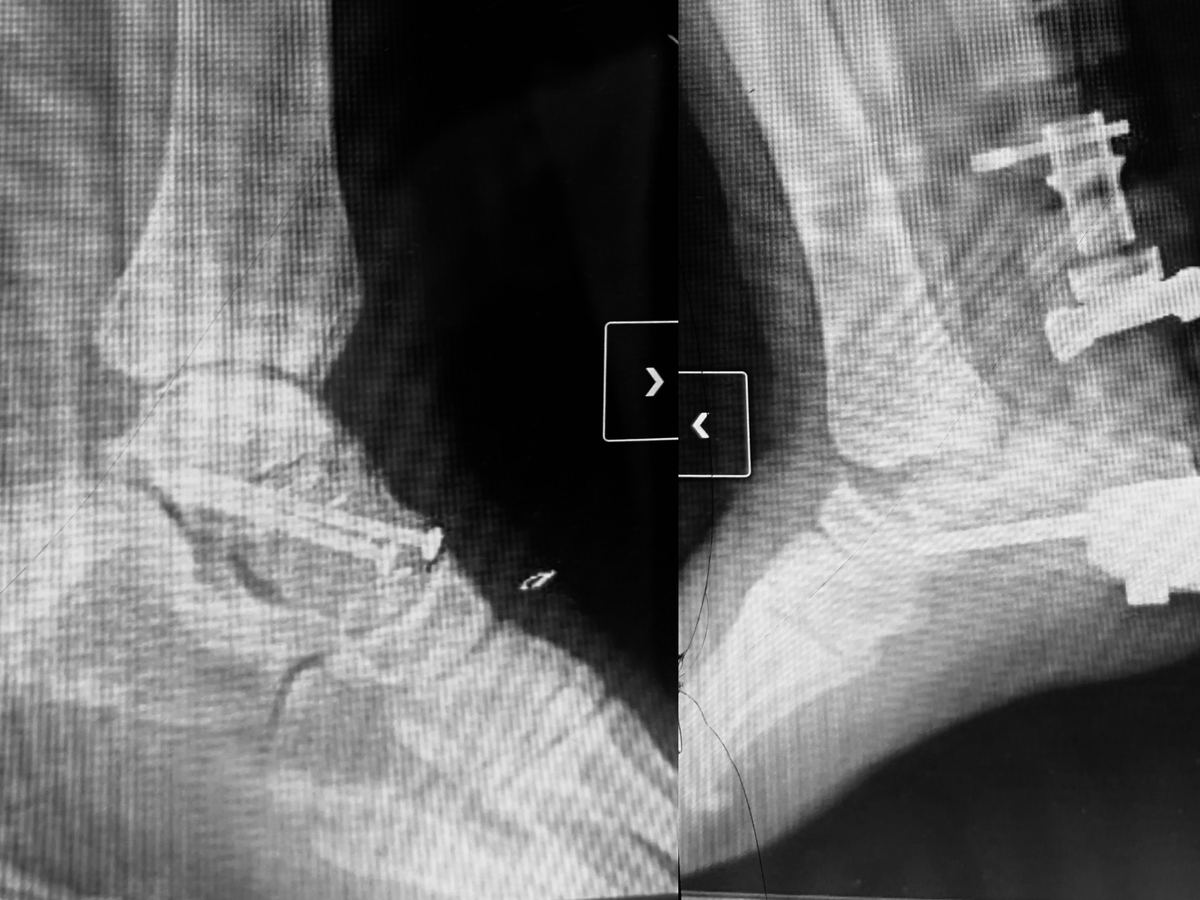

His left foot is broken and now held together with screws. His right foot suffered catastrophic damage; his talus bone popped out of his ankle, and his foot was nearly severed, held on only by tendons and skin. At the scene, I applied two tourniquets and elevated his leg to stop the bleeding by his instruction that he was able to give calmly despite the pain until paramedics arrived. When they eventually arrived, one of the paramedics foolishly stepped on his left foot, causing him immense pain. Even after yelling at him over and over, he just kept stepping on him.